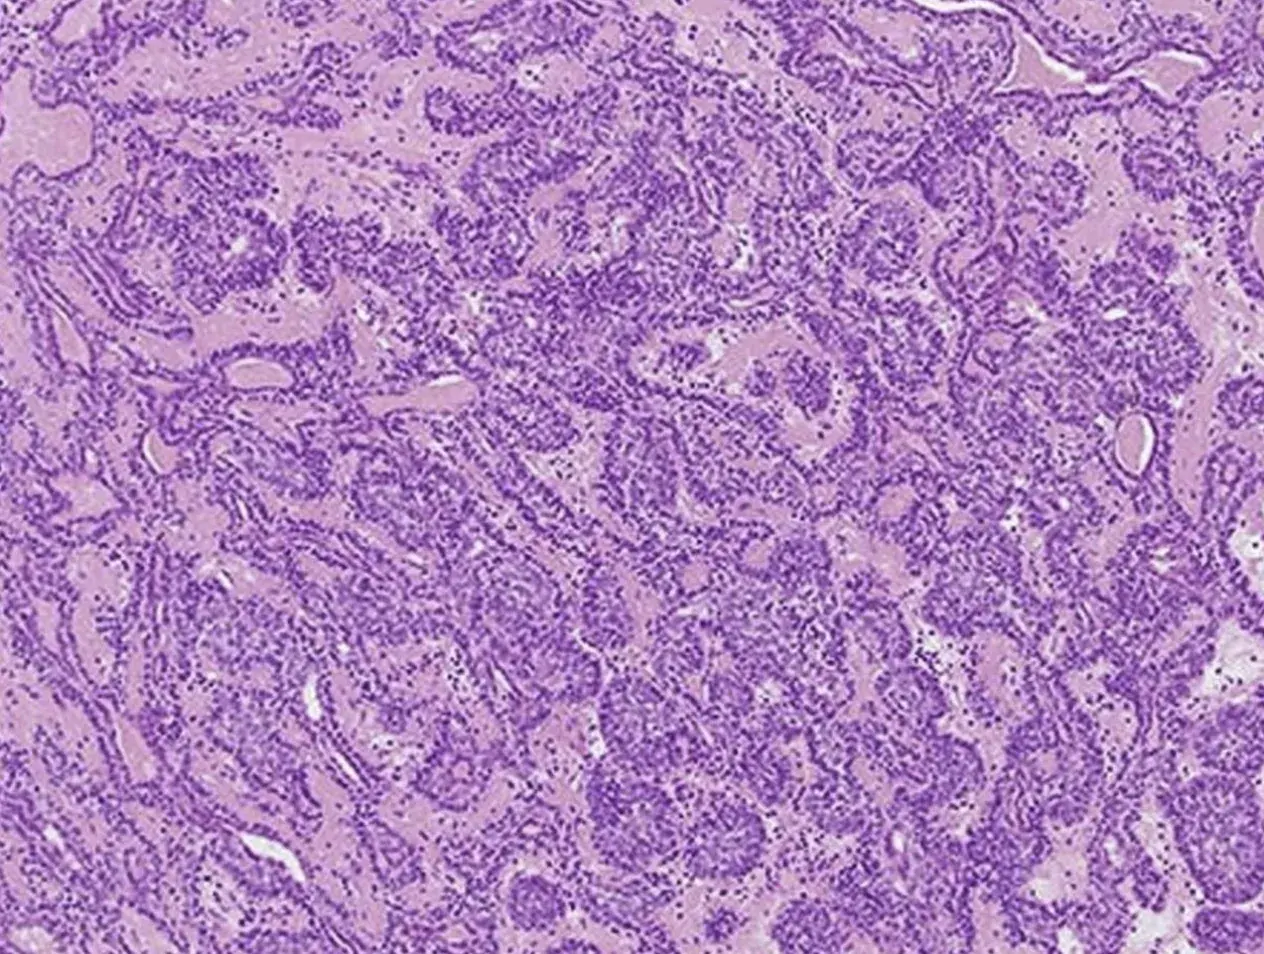

Pic: Spiradenoma presenting as a dermal nodule in chest of a 55-year old female patient.